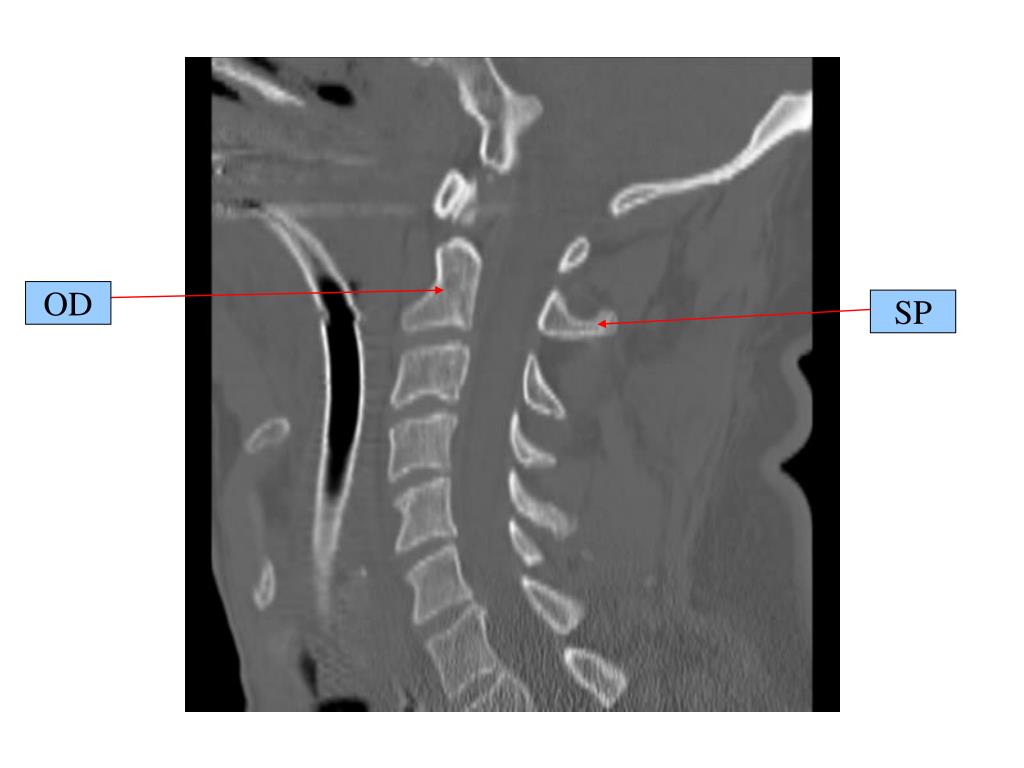

3. OD SP